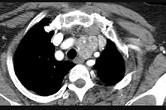

问题 40岁,女,发现颈部肿块,随吞咽上下移动,触之无搏动,咳嗽、气喘一周,请结合CT检查选择最可能的诊断()

选项 A.胸腺瘤 B.胸内甲状腺瘤 C.无名动脉瘤 D.无名动脉伸展扭曲 E.淋巴瘤

答案 B